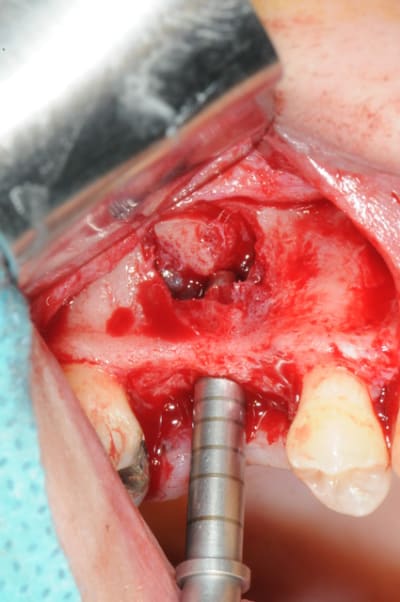

les suivantes;

- forage et transperçage de la crête sans aller trop loin...

- essayage pilier pour parallélisme

- forage à 3mm

- visualisation de la hauteur sous la membrane de Schneider

- utilisation d'un ostéotome diamètre 3.4 puis 3.8

(sous dimensionnement de diamètre par rapport à l'implant prévu :4mm)

- mise en place de l'implant

- séchage discret de la surface osseuse

- injection du Vital Os en palatin et partout autour de l'implant

- hé hé hé ... pas de membrane de recouvrement, le matériaux se suffit à lui même. d'où une petite économie substantielle pour ceux qui ont l'habitude de mettre systématiquement une membrane après un Caldwell-Luc.

- sutures...